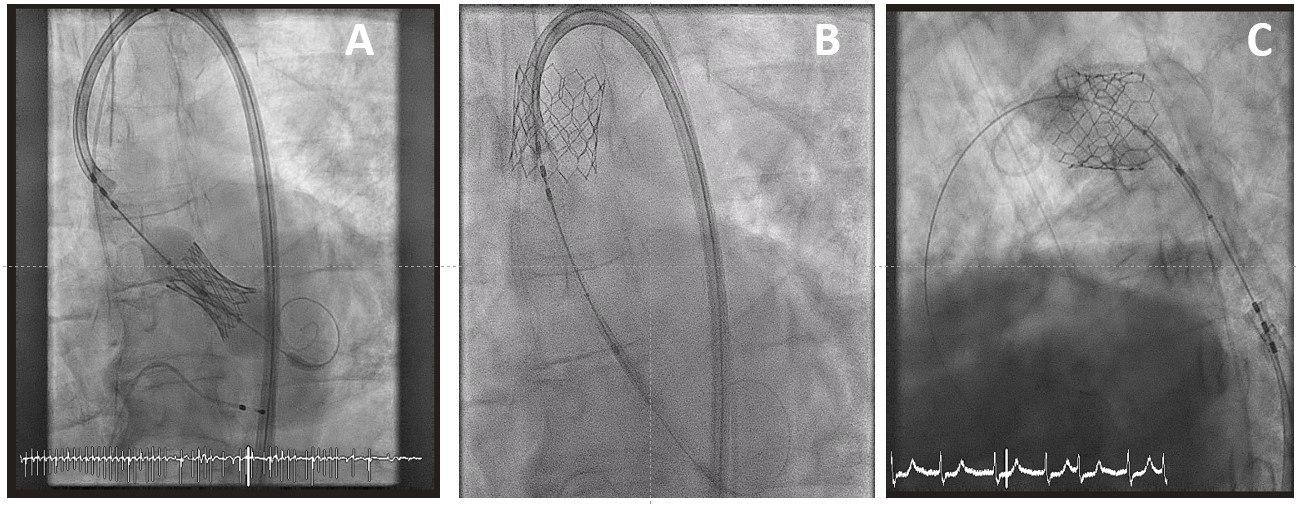

An 83-year-old man with severe aortic stenosis underwent implantation of a 29-mm SAPIEN-3 (Edwards Lifesciences) transcatheter aortic valve (TAV) appropriately sized for an aortic annulus area of 543.6 mm2. Immediately post-implantation, due to loss of capture of the rapid pacing sequence (pacing failure) during deployment (Figure 1A), the TAV lost contact with the aortic annulus and migrated to the ascending aorta (Video 1). After a brief period of rocking motion within the ascending aorta (Figure 1B), the TAV was finally embolized at the distal part of the aortic arch (Figure 1C; Videos 2 and 3). Due to a significant residual aortic valve regurgitation, an additional 29-mm balloon-expandable TAV was successfully advanced through the first TAV and deployed in the native valve (Figure 2A). Having assessed that the embolized TAV was positioned distally to the ostia of the left common carotid and the left subclavian artery with ample patency of possibly jeopardized vessels (Figure 2B), post-dilation with a 29-mm balloon was performed to secure the valve against the aortic wall (Figure 2C).